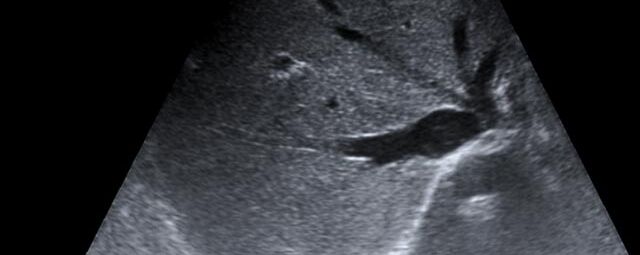

Die Sonographie ist ein bildgebendes Verfahren in der medizinischen Diagnostik, das mit Ultraschallwellen arbeitet. Ultraschall ist Schall mit einer Frequenz oberhalb der menschlichen Hörgrenze. Im medizinischen Bereich werden je nach Körperregion Ultraschallwellen in einem Frequenzbereich von ca. 3,5 – 18 Mhz verwendet. Die körpernahe Ultraschallsonde sendet durch einen piezoelektrischen Effekt kurze Schallwellenimpulse in den Körper. Ultraschall-Gel stellt den Kontakt zwischen Sonde und Körper her. Je nach Gewebeart werden diese Schallwellen im Körper unterschiedlich stark reflektiert. Anhand des zurückgesendeten Schallmusters kann das Ultraschallgerät Schnittbilder berechnen, auf denen die Organe des Körpers nach krankhaften Veränderungen untersucht werden können.